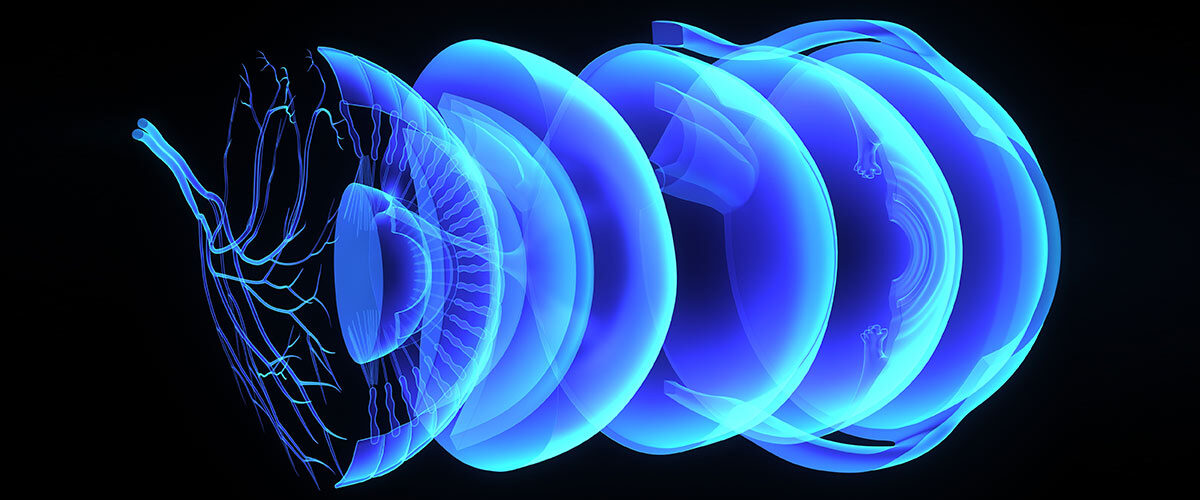

Jaga Mata Anda: Cara Melindungi Penglihatan dari Dampak Cahaya Biru

Di era digital, kita menghabiskan berjam-jam setiap hari di depan layar ponsel, komputer, atau televisi. Namun, cahaya biru yang dipancarkan oleh perangkat ini dapat menyebabkan ketegangan mata, kekeringan, […]